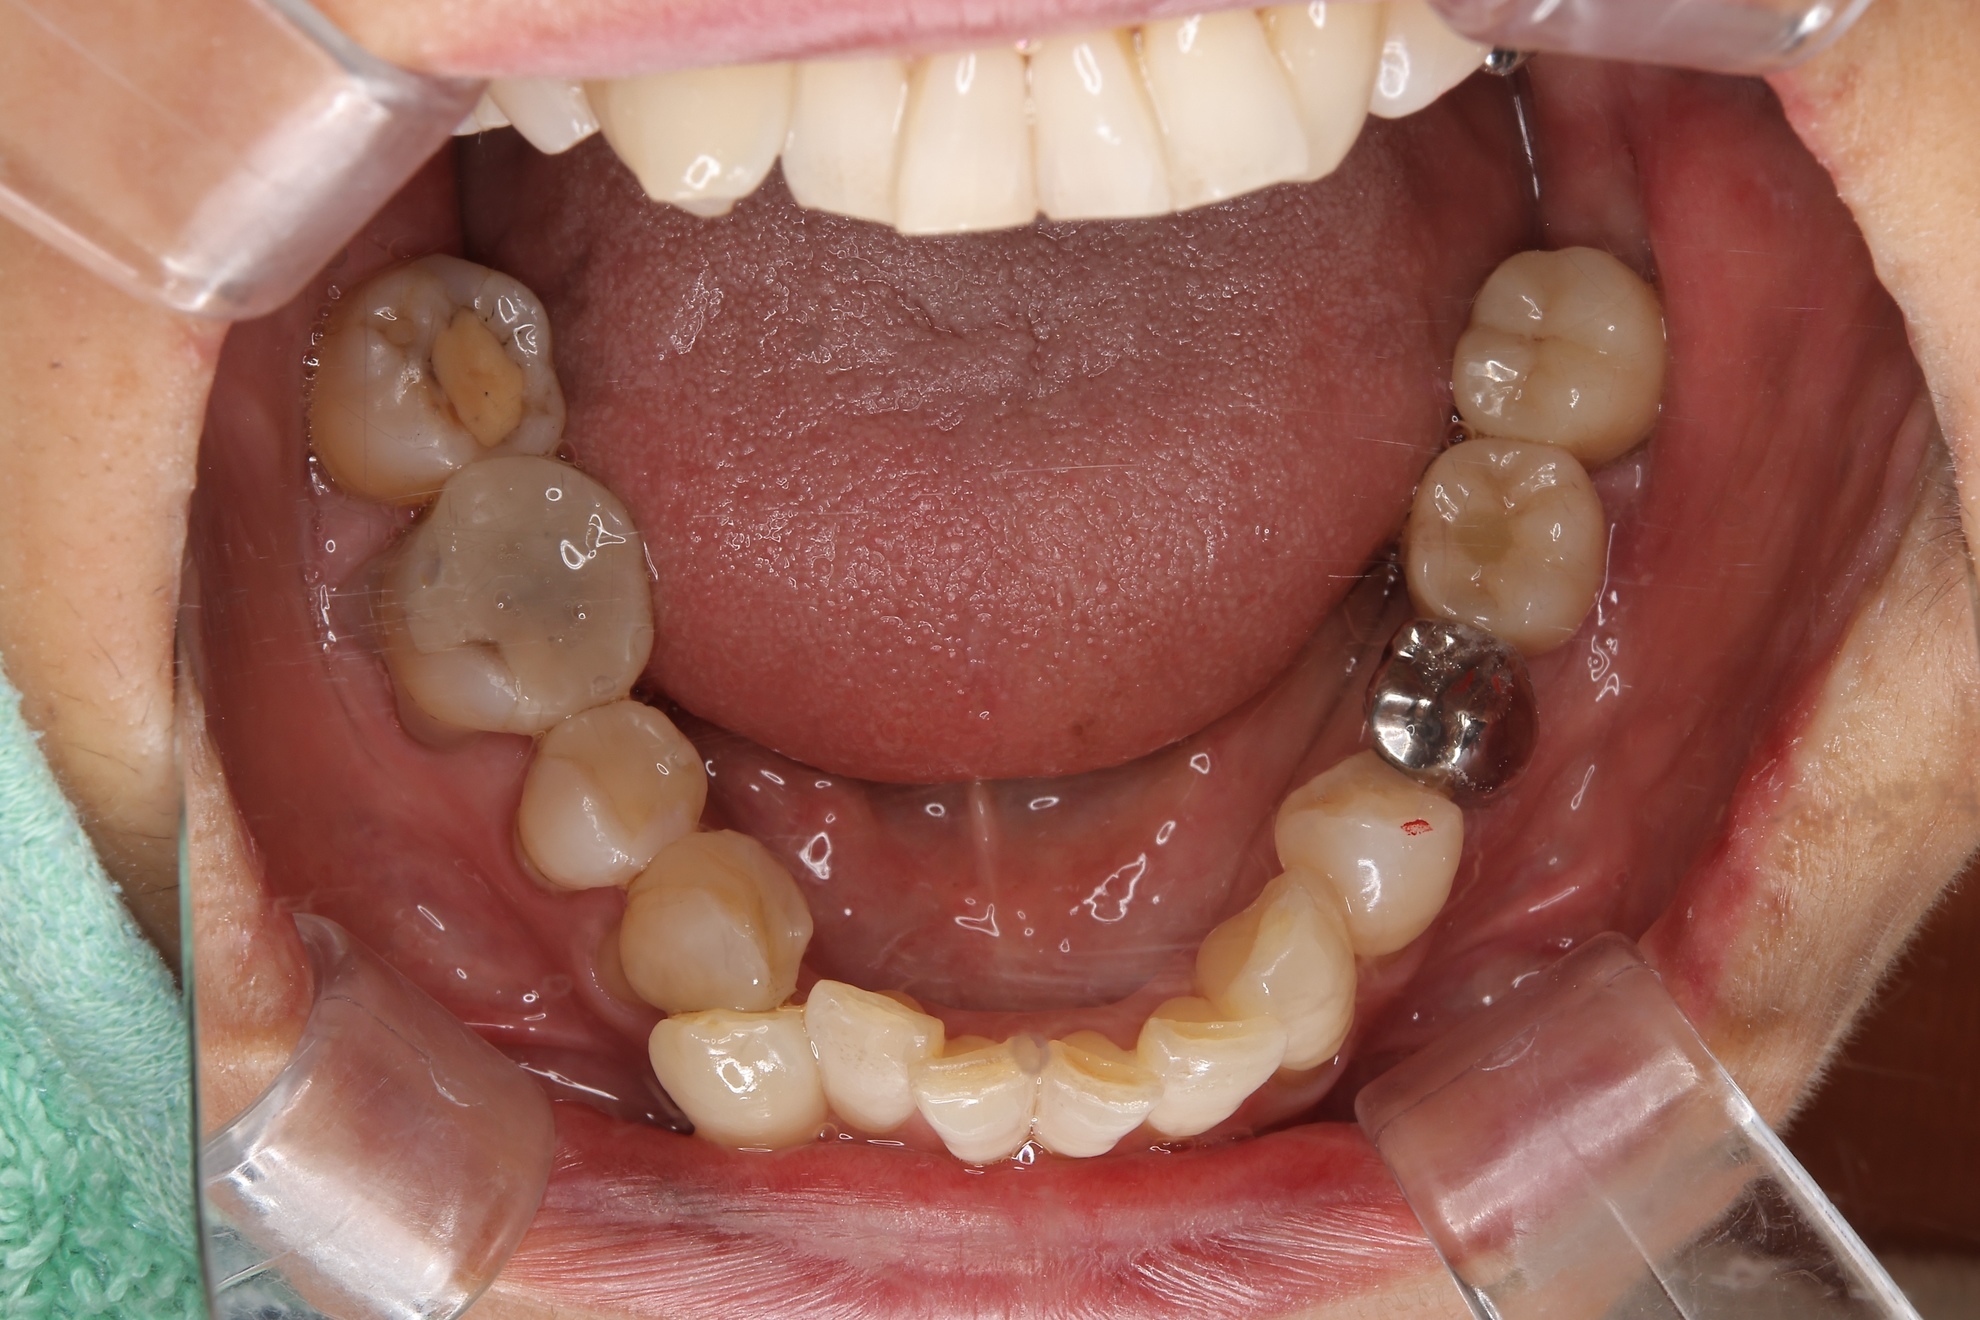

こちらの症例では、左下の奥歯2本を失った箇所に対し、以下の2つの異なるアプローチを行いました。

最終補綴終了後

最終補綴物が装着された状態です。

審美性と高い強度を持つジルコニアにて仕上げています。